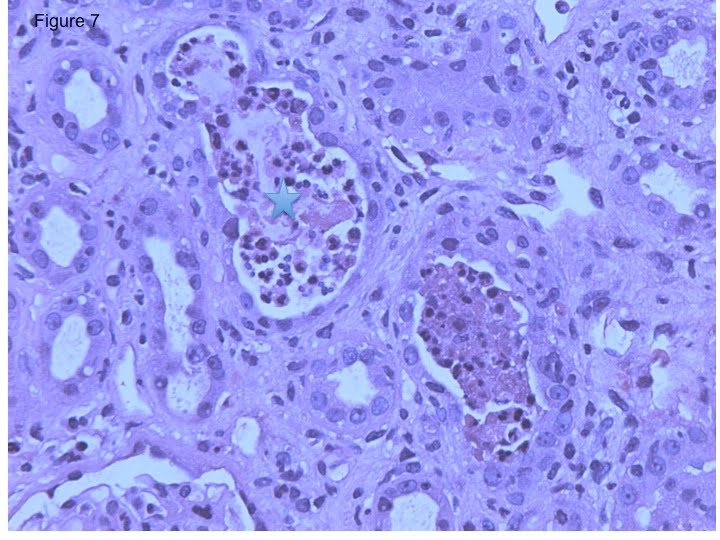

*In contrast to antibody-mediated rejection, when neutrophils are mainly concentrated within the tubular lumen rather than peritubular capillaries (Figure 7, star), then bacterial urinary infection should be high on our differential.